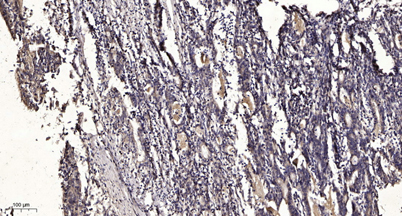

Dilutions: WB 1:500-2000;IHC-p 1:50-300; ELISA 2000-20000

Immunogen: The antiserum was produced against synthesized peptide derived from human SHP-1 around the phosphorylation site of Tyr564. AA range:530-579